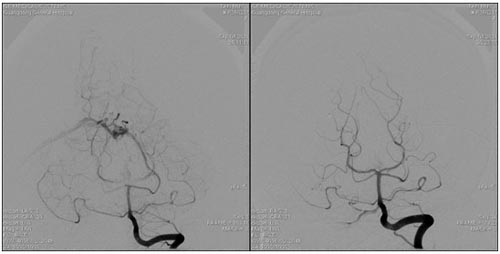

栓塞术前显影的基底动脉瘤 栓塞术后基底动脉瘤不显影